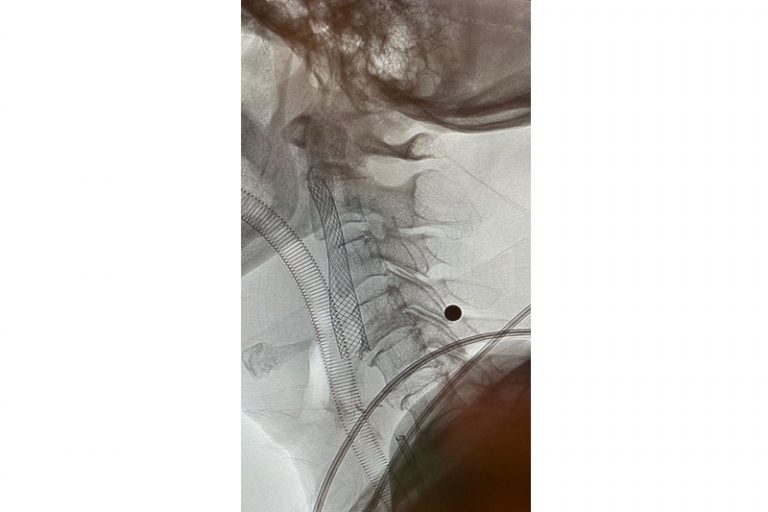

經過1小時的血管急救,所有血栓都被移除,羅先生的右頸和腦部血管都給順利打通,腦部缺血情況立即得到改善。血栓被吸取後,腦血管外科醫生發現羅先生的右頸內動脈有嚴重血管狹窄的情況,這個狹窄就是羅先生中風的主要原因。醫生因此植入血管支架來重新擴張狹窄的血管,以防止羅先生將來中風復發。全身麻醉清醒後,羅先生的大腦意識和手腳活動能力即時好轉,他其後再被送回另一間公立醫院繼續康復治療。

圖:血栓被吸取後,發現右頸內動脈血管嚴重狹窄是中風的主要原因。

圖:醫生植入血管支架來重新擴張狹窄的血管,以防止將來中風復發。